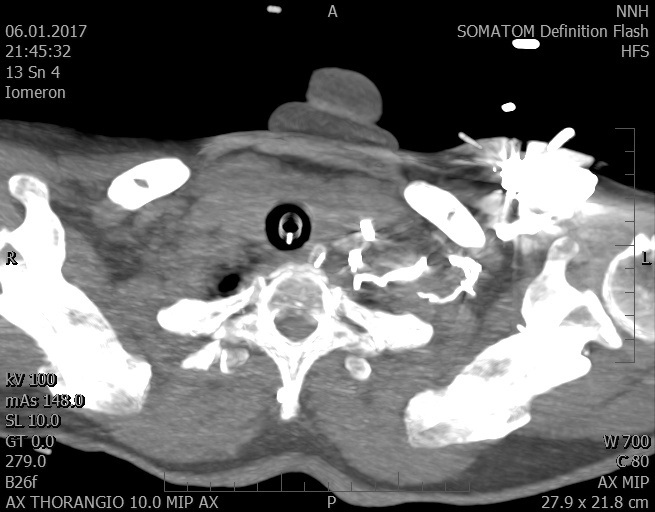

Video 2 - Echokardiograficky byla zjištěna těžká dysfunkce dilatační levé komory s nezvětšenou pravou komorou.Pro nejasnou příčinu zástavy jsme provedli i vyšetření výpočetní tomografií (CT), které vyloučilo plicní embolizaci (série 1 - soubory na konci článku). V den přijetí při přetrvávající oběhové nestabilitě byla nemocná opakovaně defibrilována pro fibrilaci komor se stabilizací rytmu po podání amiodaronu a mesocainu. Dle hemodynamických měření se jednalo o těžký kombinovaný šok. Vstupní laboratorní vyšetření bylo bez větších pozoruhodností. Posléze jsme doplnili anamnézu od příbuzných a zjistili, že pacientka užila do dvou hodin před srdeční zástavou první tabletu amoxicilinu na lehký respirační infekt. Při nevýtěžnosti vstupních vyšetření a nových anamnestických informacích jsme doplnili 14 hodin po kolapsu vyšetření koncentrace tryptázy v séru, která byla extrémně zvýšena (tabulka 2), což nás vedlo k podezření na anafylaxi.